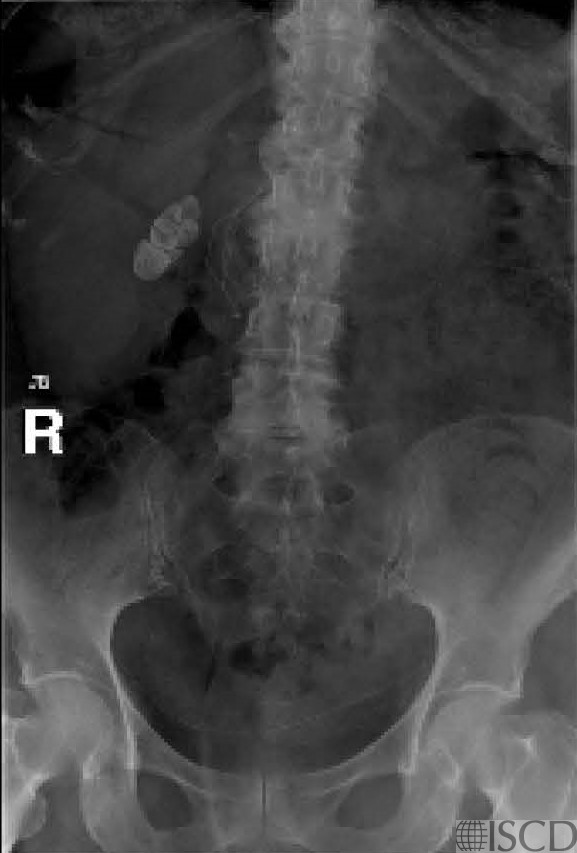

There are gallstones lateral to L1-L3 on the Hologic spine DXA scan.

The accompanying radiograph demonstrates the gallstones.

There are gallstones seen lateral to the Hologic spine on the right. The accompanying radiograph demonstrates the gallstones. The “undo” view may be checked in Hologic to confirm that the artifact is removed from the soft tissue baseline.